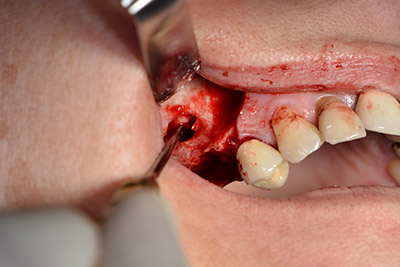

The classic incision (crestal, buccal relief) and the preparation of the mucoperiosteal flap enabled a good overview.

The next step was the sinus floor elevation with simultaneous implantation. The Implantmed also had a presetting at the first position for the buccal fenestration of the maxillary sinus wall.

The fenestration was prepared at 35,000 rpm and then the nasal mucosa were prepared in the cranial direction (Fig. 13 to 14).

The implant was then placed and the bone built up. In this case, because of the size of the augmentation region, autologous bone chips, harvested with an osseous trap as drilling chips from implantation 16 and fenestration 14, were mixed with bone replacement material.

An absorbable membrane was used as the barrier in the buccal direction and covered the augmentation. Finally, saliva-proof sutures were placed (Fig. 15 to 19).